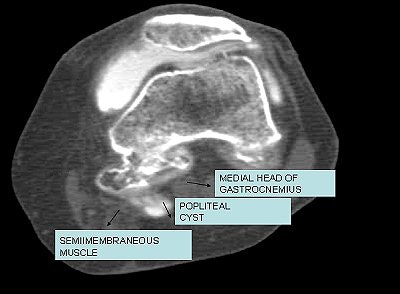

![]() |

| Iodinated contrast-enhanced (8 cc delivered to the knee joint) CT arthrogram (Sytec SRi, GE Healthcare). One-millimeter axial scans (kVp 120; mAs 80) of the joint were performed. There is extravasation of contrast in the synovial cyst between medial gastrocnemius and semimembranosus tendon. Image courtesy of Dr. Shamim Malk. |

At arthrogram, a Baker's cyst and a small medial meniscus tear was diagnosed. The patient underwent excision of the Baker's cyst and medial meniscectomy as the meniscal tear was much larger than perceived on the arthrogram. Her recovery was uneventful and she rested for a full month after the operation.